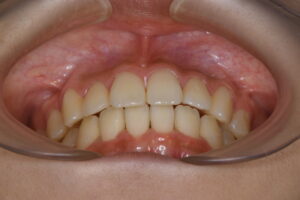

実際の症例紹介(20代女性/裏側ワイヤー矯正)

治療前

治療後

・主訴:八重歯と前歯の突出

・治療法:裏側からのワイヤー矯正(リンガル)

・治療期間:約1年半〜2年(目安)

・予想される副作用・リスク:装置装着後の違和感・疼痛、発音のしづらさ、一時的な咀嚼効率低下、ブラッシング不良によるむし歯・歯周病リスク など

※写真は代表的な症例です。口腔内の状態により治療法や期間は異なります。詳細は初診相談でご説明します。